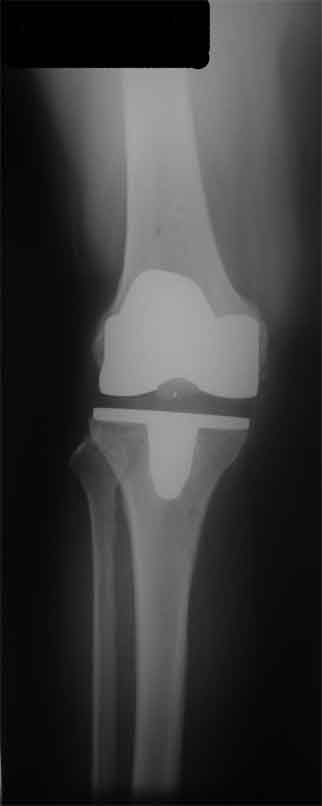

Стрессовый снимок

Оперирована пациентка 42 лет, избыточного веса. Выполнено б/ц протезированние коленного сустава эндопротезом LCS. Послеоперационный период гладкий, в срок 2 мес. после операции объем движений удовлетворительный, сгибание до острого угла, разгибание полное. В 3,5 мес. во время падения подвернула ногу, после чего появилась. клиника медиолатеральной нестабильности. В течении 3 недель фиксация в туторе. При повторном осмотре жалобы на дискомфорт в коленном суставе, «щелканье», неустойчивость в суставе. Вопросы/варианты дальнейшей тактики лечения пациентки.

1) Существует ли способы восстановления внутренней боковой связки на фоне протезированного коленного сустава и как добиться равномерного ее натяжения при всех углах сгибания.

2) Ревизия с установкой более связанного протеза (constrained)